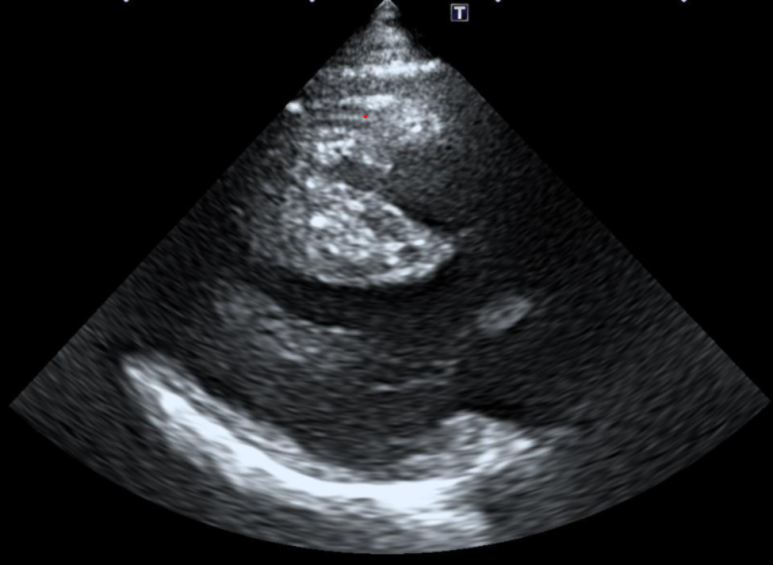

심낭염